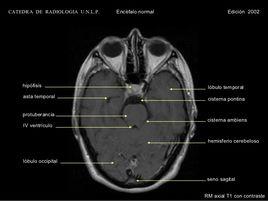

環池(cisternaambiens)位於海馬旁回與大腦腳之間,呈弧狀包繞中腦外側面,內側為大腦腳和腳間池,外側幕上為內側顳葉及海馬、溝回、海馬旁回,幕下為小腦的方葉,下界與橋小腦池相鄰,向前與大腦腳池相通,底壁位於視束的下面或外下面,約平對小腦幕游離緣水平。環池可分為體部和翼部。環池向上延伸部稱為環池翼:從顳葉溝回伸出的腦池、越過丘腦枕前內側到達室間孔附近的帆間區;體部即下部較豎直的部分。環池的最大寬度為3.5~28.0mm。環池內容物有大腦後動脈P2段及其供應中腦的一些分支,Rosenthal基底靜脈以及小腦上動脈、脈絡膜後內外側動脈、四疊體動脈、橋中腦外側靜脈和滑車神經。其中脈絡膜前動脈、Rlsenthal基底靜脈及大腦後動脈P2段三者主要位於環池前部,一般脈絡膜前動脈及Rosenthal基底靜脈在池頂走行。

大腦後動脈是基底動脈的終支,在中腦腹側起自基底動脈終末的分叉處,位於中腦、端腦和間腦結合處,繞中腦向外走行,分四段。P2也稱環池段,自後交通動脈及大腦後動脈交接處延伸至中腦後方,剛好在小腦幕上方繞過大腦腳,大腦後動脈此段在環池底向後繞行與視束及基底靜脈平行,常有一輕度下凸。P2段沿途發出四疊體動脈、丘腦膝狀體動脈、脈絡膜後內外側動脈、顳下前動脈、顳下中動脈、顳下後動脈等分支,主要供應四疊體、外側膝狀體、脈絡膜等結構。

小腦上動脈起於基底動脈末端,沿小腦與腦幹之間向外行走,至小腦幕內下方,主幹與滑車神經交叉後行於其上方,小腦上動脈走行過程中逐漸發出小腦支和腦幹支,分布於小腦上面和中腦、腦橋背面。

滑車神經是惟一發自腦幹背側的腦神經,在顱內的行徑最長,且最為細小,滑車神經在小腦幕側方的走行即在環池內的走行,環池的滑車神經與幕緣關係密切,在環池內大腦後動脈和小腦上動脈之間前行,前段在小腦幕游離緣內走行,幕上直視不易識別。

基底靜脈在前穿質下面由大腦中深靜脈和大腦前靜脈匯合而成,經海馬回溝上方進入環池,在環池內接收側腦室下角的靜脈後繞大腦腳向後注入大腦大靜脈。在環池內大腦後動脈和滑車神經位於基底靜脈外側,小腦上動脈位於基底靜脈的外下方,四者關係密切。基底靜脈緊貼中腦,而大腦後動脈和小腦上動脈浸於環池的腦脊液中,所以中腦占位病變常使基底靜脈變形。